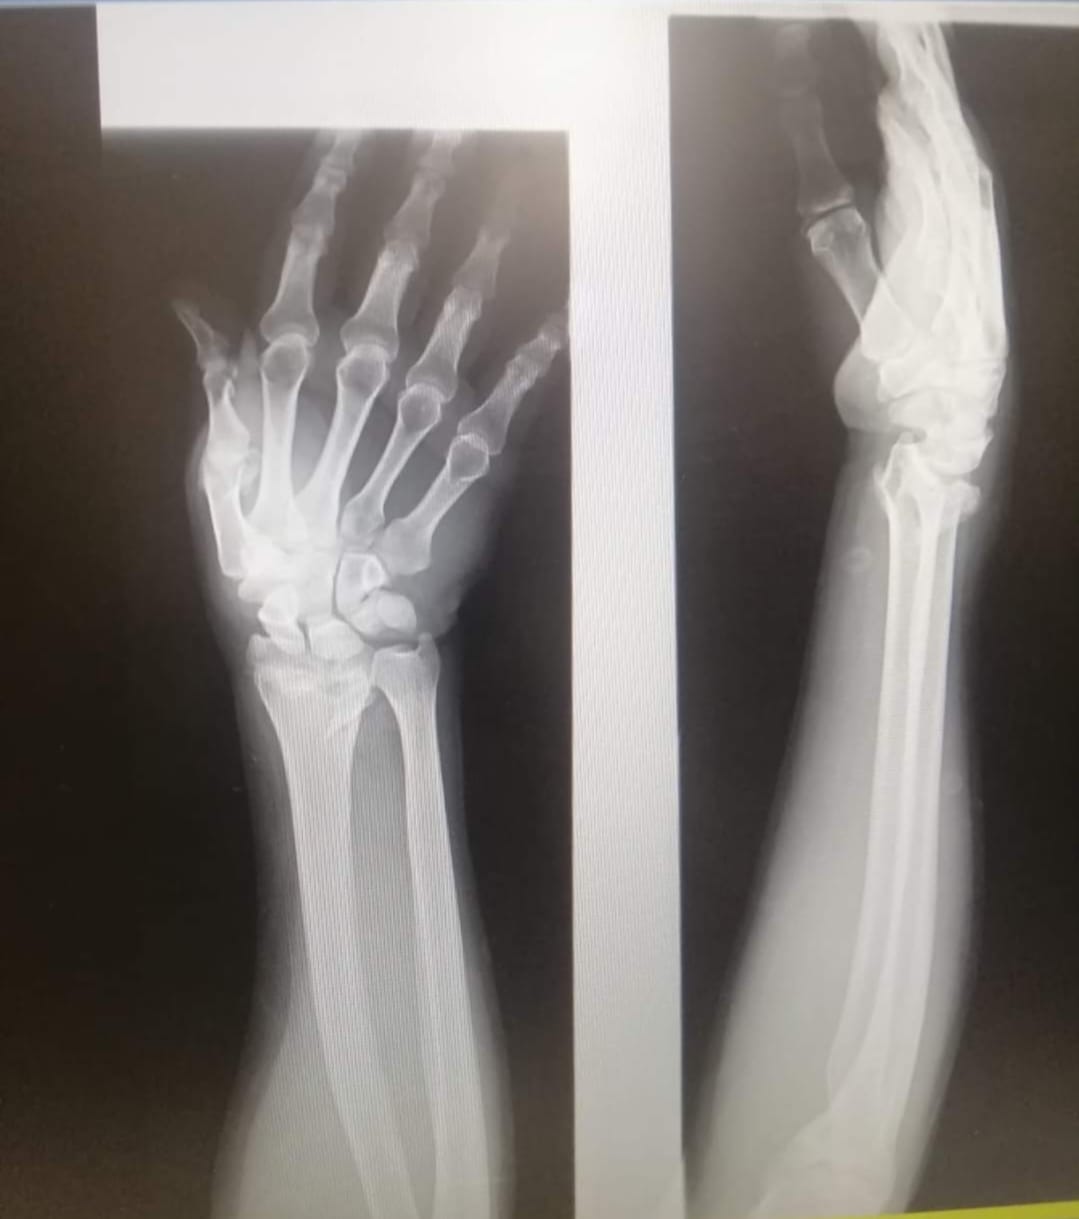

يقوم بعمليات تثبيت الكسور المعقدة بشكل طاريء وتبديل المفاصل بشكل مبرمج مما خفف على المواطنين البحث عن أسرة في مستشفيات مركزية رغم صعوبة عمليات العظام من الناحية التقنية في المستشفيات النائية إضافة الى استقبال اعداد كبيرة بالعيادات ومعالجة جميع المرضى بالطرق المثلى انه الدكتور الانسان البارع والمتميز يزيد البريزات طبيب العظام في مستشفى الاميرة سلمى / ذيبان عيادة العظام علماً بأنه كان مستشفى تحويلي منذ تاسيسه والدكتور البربزات وقبل اربع سنوات في عام 2020 منذ انتقاله للمستشفى يقوم بهذه العمليات ومن بينها عمليات نوعية لمرضى يعانون من كسور معقدة في الترقوة واجراء عمليات دقيقة ومعقدة لكسور لمرضى في مختلف أنحاء الجسم وعمليات تثبيت الكسور المعقدة وتركيب المفاصل وغيرها الكثير والديسك " وآلامه وتبعاته وعلاجه وإجراء عمليات معقده وصعبه.

وأجرى الدكتور البريزات عمليات كبرى في جراحة العظام والتي تحتاج إلى مراكز متقدمة ومتطورة. وكذلك العمل على تثبيت أغلب انواع الكسور بطريقة طارئة وتبديل المفاصل بطريقة مبرمجة بما يتناسب مع امكانات المستشفى والتي هي جزء من العمليات الدورية بمستشفى الاميرة سلمى في ذيبان والتي تخفف العبئ على المستشفيات المركزية وعلى المواطن في آن واحد.

وعبر كثير من المرضى وذويهم عن عظيم شكر هم وامتنانهم للدكتور البريزات على ما بذله ويبذله من جهود كبيرة واستثنائية في تعامله مع المرضى والمراجعين ومتابعته الحثيثة لهم والاطمئنان عليهم والتي تكللت جميعها بالنجاح وله الدور الكبير برفع كفاءة قسم العظام بالمستشفى بشكل عام والذي أصبح متطوراً بالقيام بالعمليات مثل تثبيت الكسور المعقدة و تركيب المفاصل و غيرها.